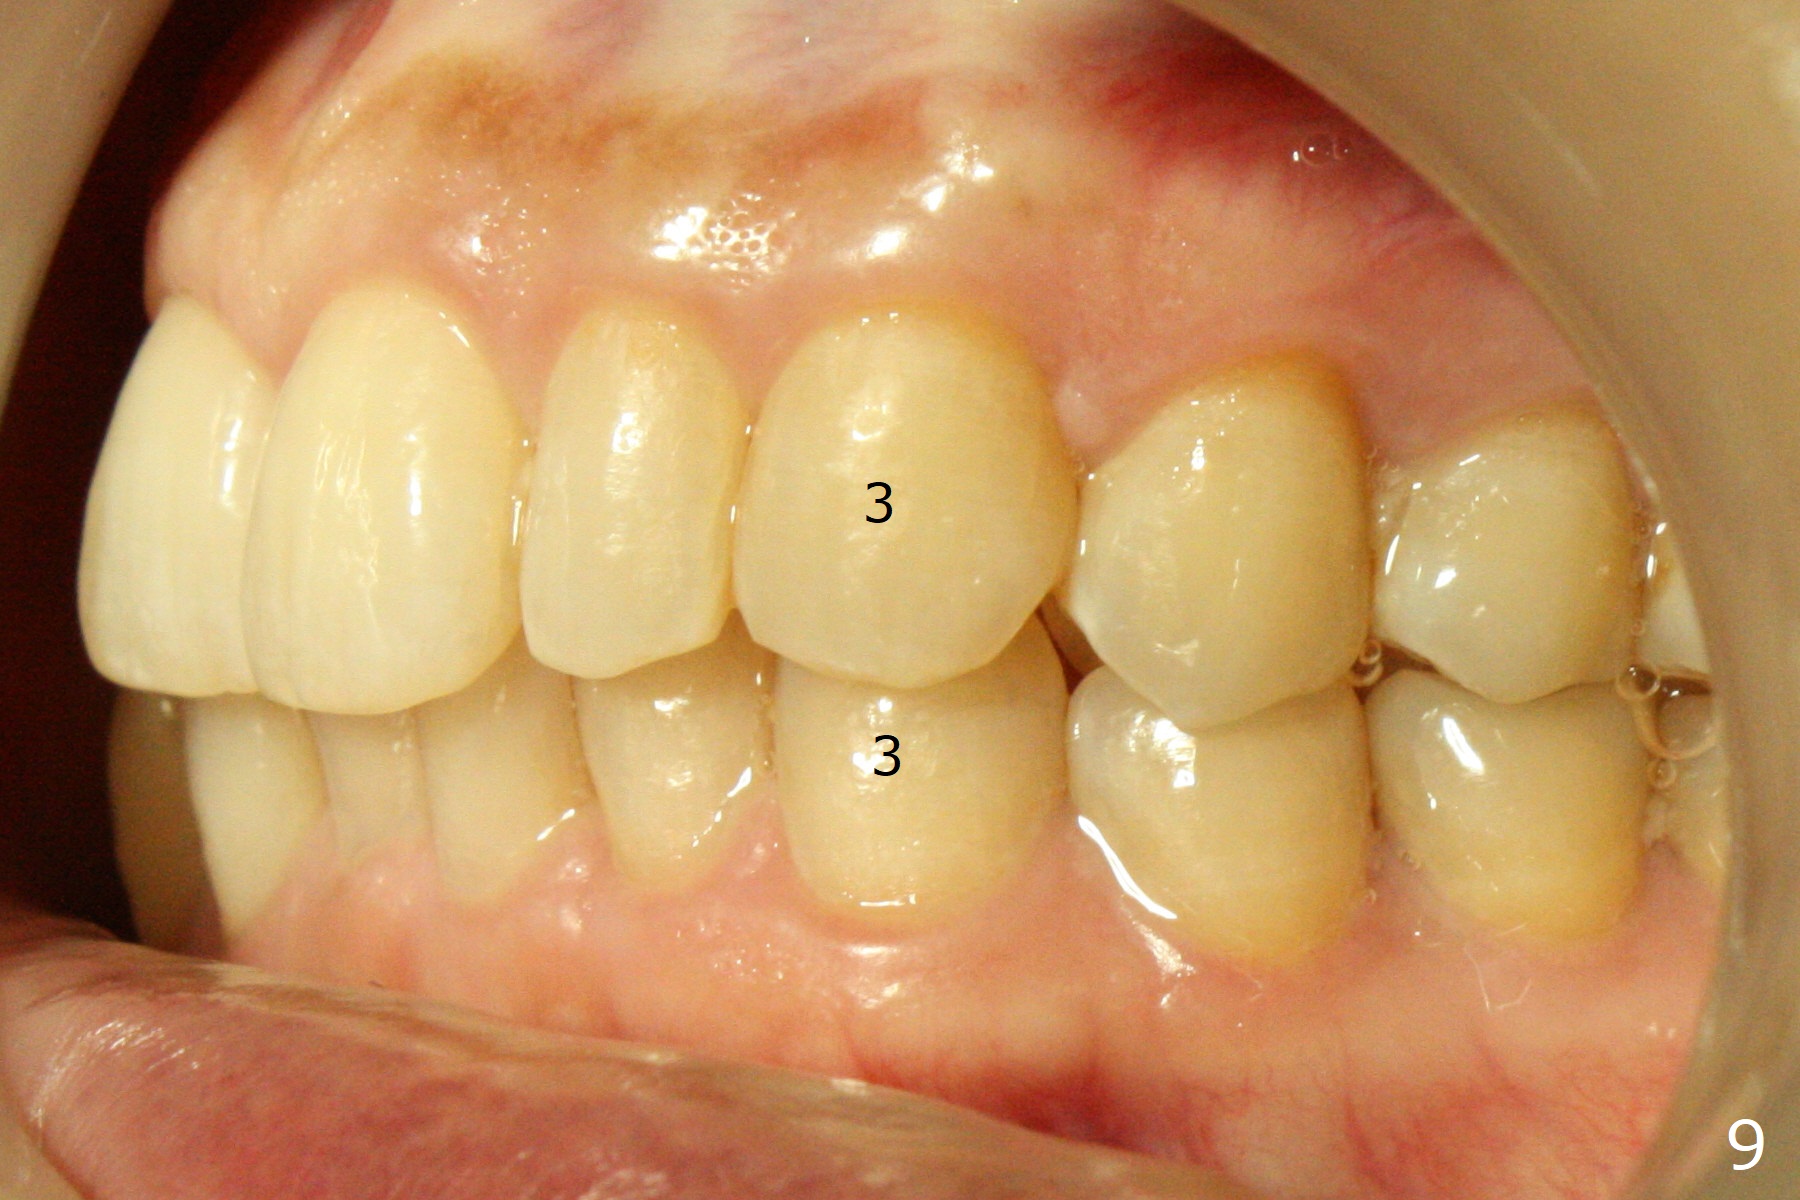

A 54-year-old woman (dento-phobic) will return for banding and bracketing 1.5 months post UR2 extraction with socket preser-vation. Lip strain is absent or minimal(Fig.1). The upper dental midline deviates to the right (Fig.2). Profile is within normal limit (Fig.3). UR3 is in cross bite (Fig.4). Cephalmetric X-ray apparently shows normal profile (Fig.5). Occlusion appears to be Class II in canine and molar (Fig.7,9, Class II Division II Malocclusion). The upper and lower dental midlines mismatch (Fig.8). UL2 is a peg lateral (Fig.10), while the lower anteriors are crowded (Fig.11). Arch wire sequence is conducted and let the timid patient decide whether the 2nd part of treatment should restore ideal occlusion with UR2 implant and UL2 veneer or simply close diastemata. Take PAs for the anteriors prior to banding to follow up root resorption during treatment.